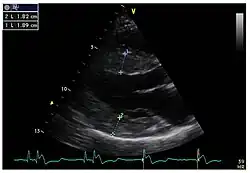

Herzschädigung

A Linksventrikuläre Hypertrophie (LVH) bei einem 51-jährigen dialysepflichtigen Patienten mit zerebrovaskulärer Beteiligung.

B 56-jähriger Patient mit hypertropher Kardiomyopathie und Herzrhythmusstörung, Leukoaraiose sowie Transplantatniere.

C Late-Enhancement-Messung nach der Gabe eines gadoliniumhaltigen Kontrastmittels bei einer 63-jährigen dialysepflichtigen Patientin.

Etwa 40 bis 60 % der Morbus-Fabry-Patienten zeigen kardiale Symptome wie linksventrikuläre Hypertrophie (LVH, Verdickung der Herzwände der linken Herzkammer), Herzrhythmusstörung (Arrhythmie), Angina Pectoris (anfallsartiger Schmerz in der Brust) und Dyspnoe (erschwerte Atemtätigkeit).[78][80][81][82][83] Die Herzrhythmusstörung und die beeinträchtigte Herzfrequenzvariabilität werden vom Sinusknoten, dem Erregungsleitungssystem, und einer Störung des Gleichgewichts zwischen sympathischem und parasympathischem Tonus hervorgerufen. Diastolische Dysfunktionen und linksventrikuläre Hypertrophien sind wichtige Symptome des Morbus Fabry. Für Männer sind diese Symptome grundsätzlich schwerwiegender als für Frauen. Myokardischämien (Durchblutungsstörungen des Herzmuskels) sind die Folge einer schlechten Koronardurchblutung.[84]

Die linksventrikulären strukturellen Veränderungen des Herzens finden sich bei Morbus-Fabry-Patienten häufig. Mittels Echokardiografie (Ultraschalluntersuchung des Herzens) oder kardialer Magnetresonanztomographie (MRT) können die meist konzentrischen Hypertrophien[80][81] sichtbar gemacht werden. Da mit zunehmendem Alter durch die Ersatzfibrose die linksventrikuläre Hinterwand des Herzens immer dünner wird, ist die Messung der Septumdicke – das ist die Stärke der Scheidewand zwischen linker und rechter Herzhälfte – besonders wichtig. Unabhängig von den strukturellen Veränderungen scheint die Systole, die Phase, in der das Blut aus der linken und rechten Herzkammer herausgepresst wird, bei der Messung mit konventionellen Methoden weitgehend erhalten zu bleiben.[80][81][82][91] Die durch Morbus Fabry verursachte Kardiomyopathie ist durch eine reduzierte Kontraktion und Relaxation des Herzmuskels gekennzeichnet. Gewebedoppler (sowohl tissue velocity imaging als auch strain rate imaging) kann die Herzmuskelfunktion quantifizieren.[7][92] Mit dieser Methode kann die Kardiomyopathie noch vor der Entwicklung einer linksventrikulären Hypertrophie diagnostiziert werden.[91][93]